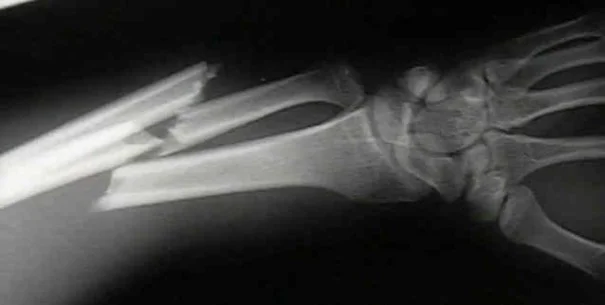

- Trauma

Trauma

- Traumatic